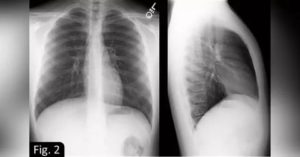

Для выявления причин появления ограниченного затемнения легочного поля, необходимо выполнить снимок в двух направлениях – в прямой проекции и боковой.

По результатам полученных изображений, важно оценить какова локализация очага затемнения.

Если тень на всех снимках находится внутри легочного поля, и сходится размерами с его контурами или имеет меньший объем, логично предположить поражение легкого.

При затемнении, примыкающем широким основанием к диафрагме или органам средостения можно диагностировать внелегочные патологии (жидкостные включения в плевральной полости). Другой критерий оценки ограниченных затемнений – это размер. В этом случае следует рассматривать два возможных варианта:

На рентгеновском снимке ограниченное затемнение легких в двух проекциях